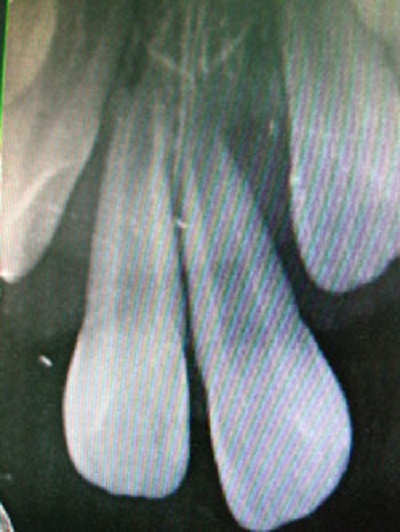

Khám lâm sàng cho thấy: gai nướu răng cửa hàm trên sưng đỏ, 2 răng cửa hàm trên bên phải lung lay độ 3, răng cửa hàm trên bên trái lung lay độ 4, cả 2 răng này tụt nướu nhiều, lộ cổ răng 1.3 mm. Chụp phim Xquang thấy tiêu xương nhiều ở vùng cổ răng, răng cửa hàm trên bên trái trồi khỏi ổ răng 1/3 chiều dài chân răng.

Răng bé khi chưa được nắn chỉnh đúng phương pháp. |

Nguyên nhân xảy ra hậu quả trên là do bé đã bị điều trị chỉnh răng sai phương pháp. Lý do thứ nhất là dùng thun cột 2 răng cửa với lực quá mạnh sẽ làm tiêu xương theo hướng lực kéo, phần khoảng trống còn lại không kịp tạo xương để bù đắp nên làm cho răng lung lay và đau nhức nhiều.

Lý do thứ hai là do hình dạng răng thon nhỏ về phía cổ răng nên thun cột có khuynh hướng co trượt về phía cổ răng gây đứt dây chằng nha chu, gây tiêu xương quanh cổ răng và làm răng trồi về phía mặt nhai. Nếu để muộn hơn, hai răng của bé sẽ tự văng ra khỏi xương hàm, bé sẽ vĩnh viễn mất hai răng này.